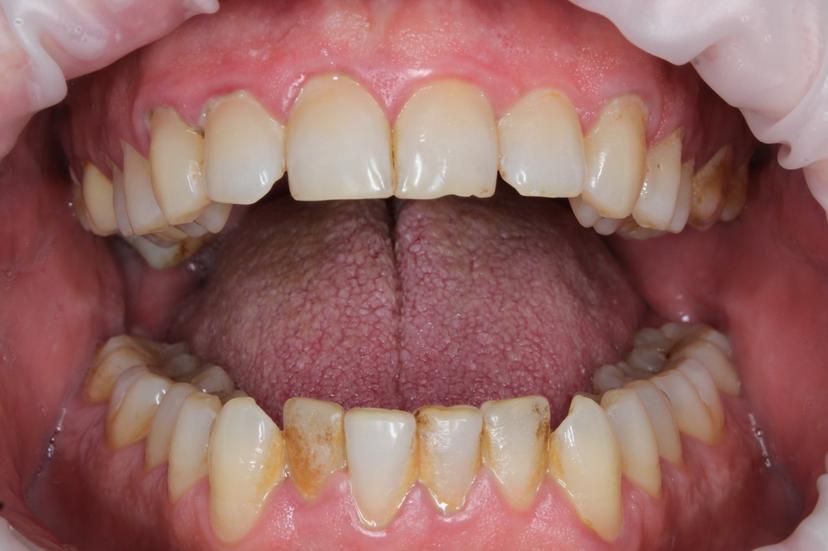

Де- и минерализованные зубные отложения пациентки с ортодонтической конструкцией. Комплексная профессиональная гигиена ультразвуковым скейлером и системой AirFlow

Ортодонтическое лечение очень важно проводить рука об руку с профилактический гигиеной полости рта. Ортодонтические аппараты создают зоны ретенции зубного налета, который проблематично убрать самостоятельно в домашних условиях.